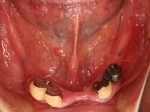

片側2歯欠損 主訴-入れ歯を使ってみたが違和感強くてダメ。固定のものにしたい。術前下顎口腔内(鏡像)